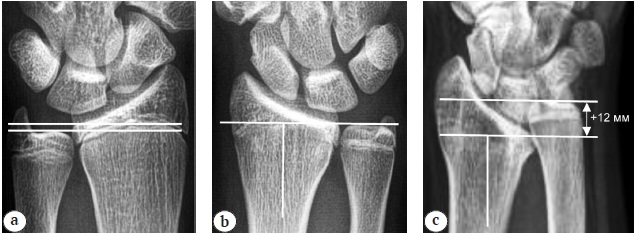

In pediatric patients aged 9–11 years, we measured the Hafner RUI [20], and in pediatric patients aged 12–17 years, the measurement was performed as in the adult population (Fig. 5).

Fig. 5. X-ray of the wrist joint in direct projection. Radial-ulnar index (measurement according to Hafner): a — distance from the most proximal point of the metaphysis of the ulna to the most proximal point of the metaphysis of the radius; b — distance from the most distal point of the metaphysis of the ulna to the most distal point of the metaphysis of the radius

Hafner et al. proposed a method for determining the RUI in pediatric patients aged 1.5–15 years by measuring the distance between the most proximal and most distal points of the growth zones of the distal forearm bones. This measurement method is ideal for children without epiphyseal ossification, but has limitations in older pediatric patients [20].

Goldfarb et al. stated that the method of measuring the RUI in adolescents aged >12 years using the standard adult technique is accurate and reliable, and the mean readings are close to those in adult patients [29].